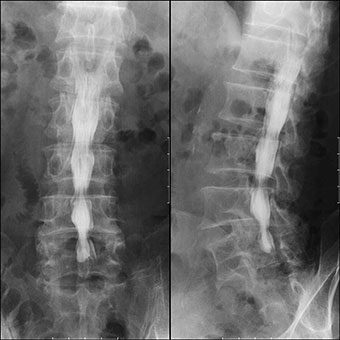

消化管造影検査

バリウムなどの造影剤を使用して、食道造影検査・胃造影検査や注腸検査を行っています。